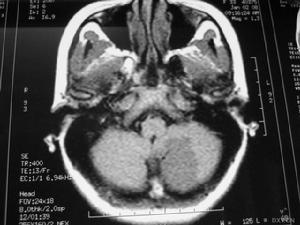

4、顱腦CT可見腦內大小不等、邊界不清的低密度灶。

5、放射學檢查:常規頭顱放射學檢查對散發性腦炎的診斷無重要價值。頭顱CT有時可見大腦半球多個散在的軟化灶,對排除占位性病變有一定意義。